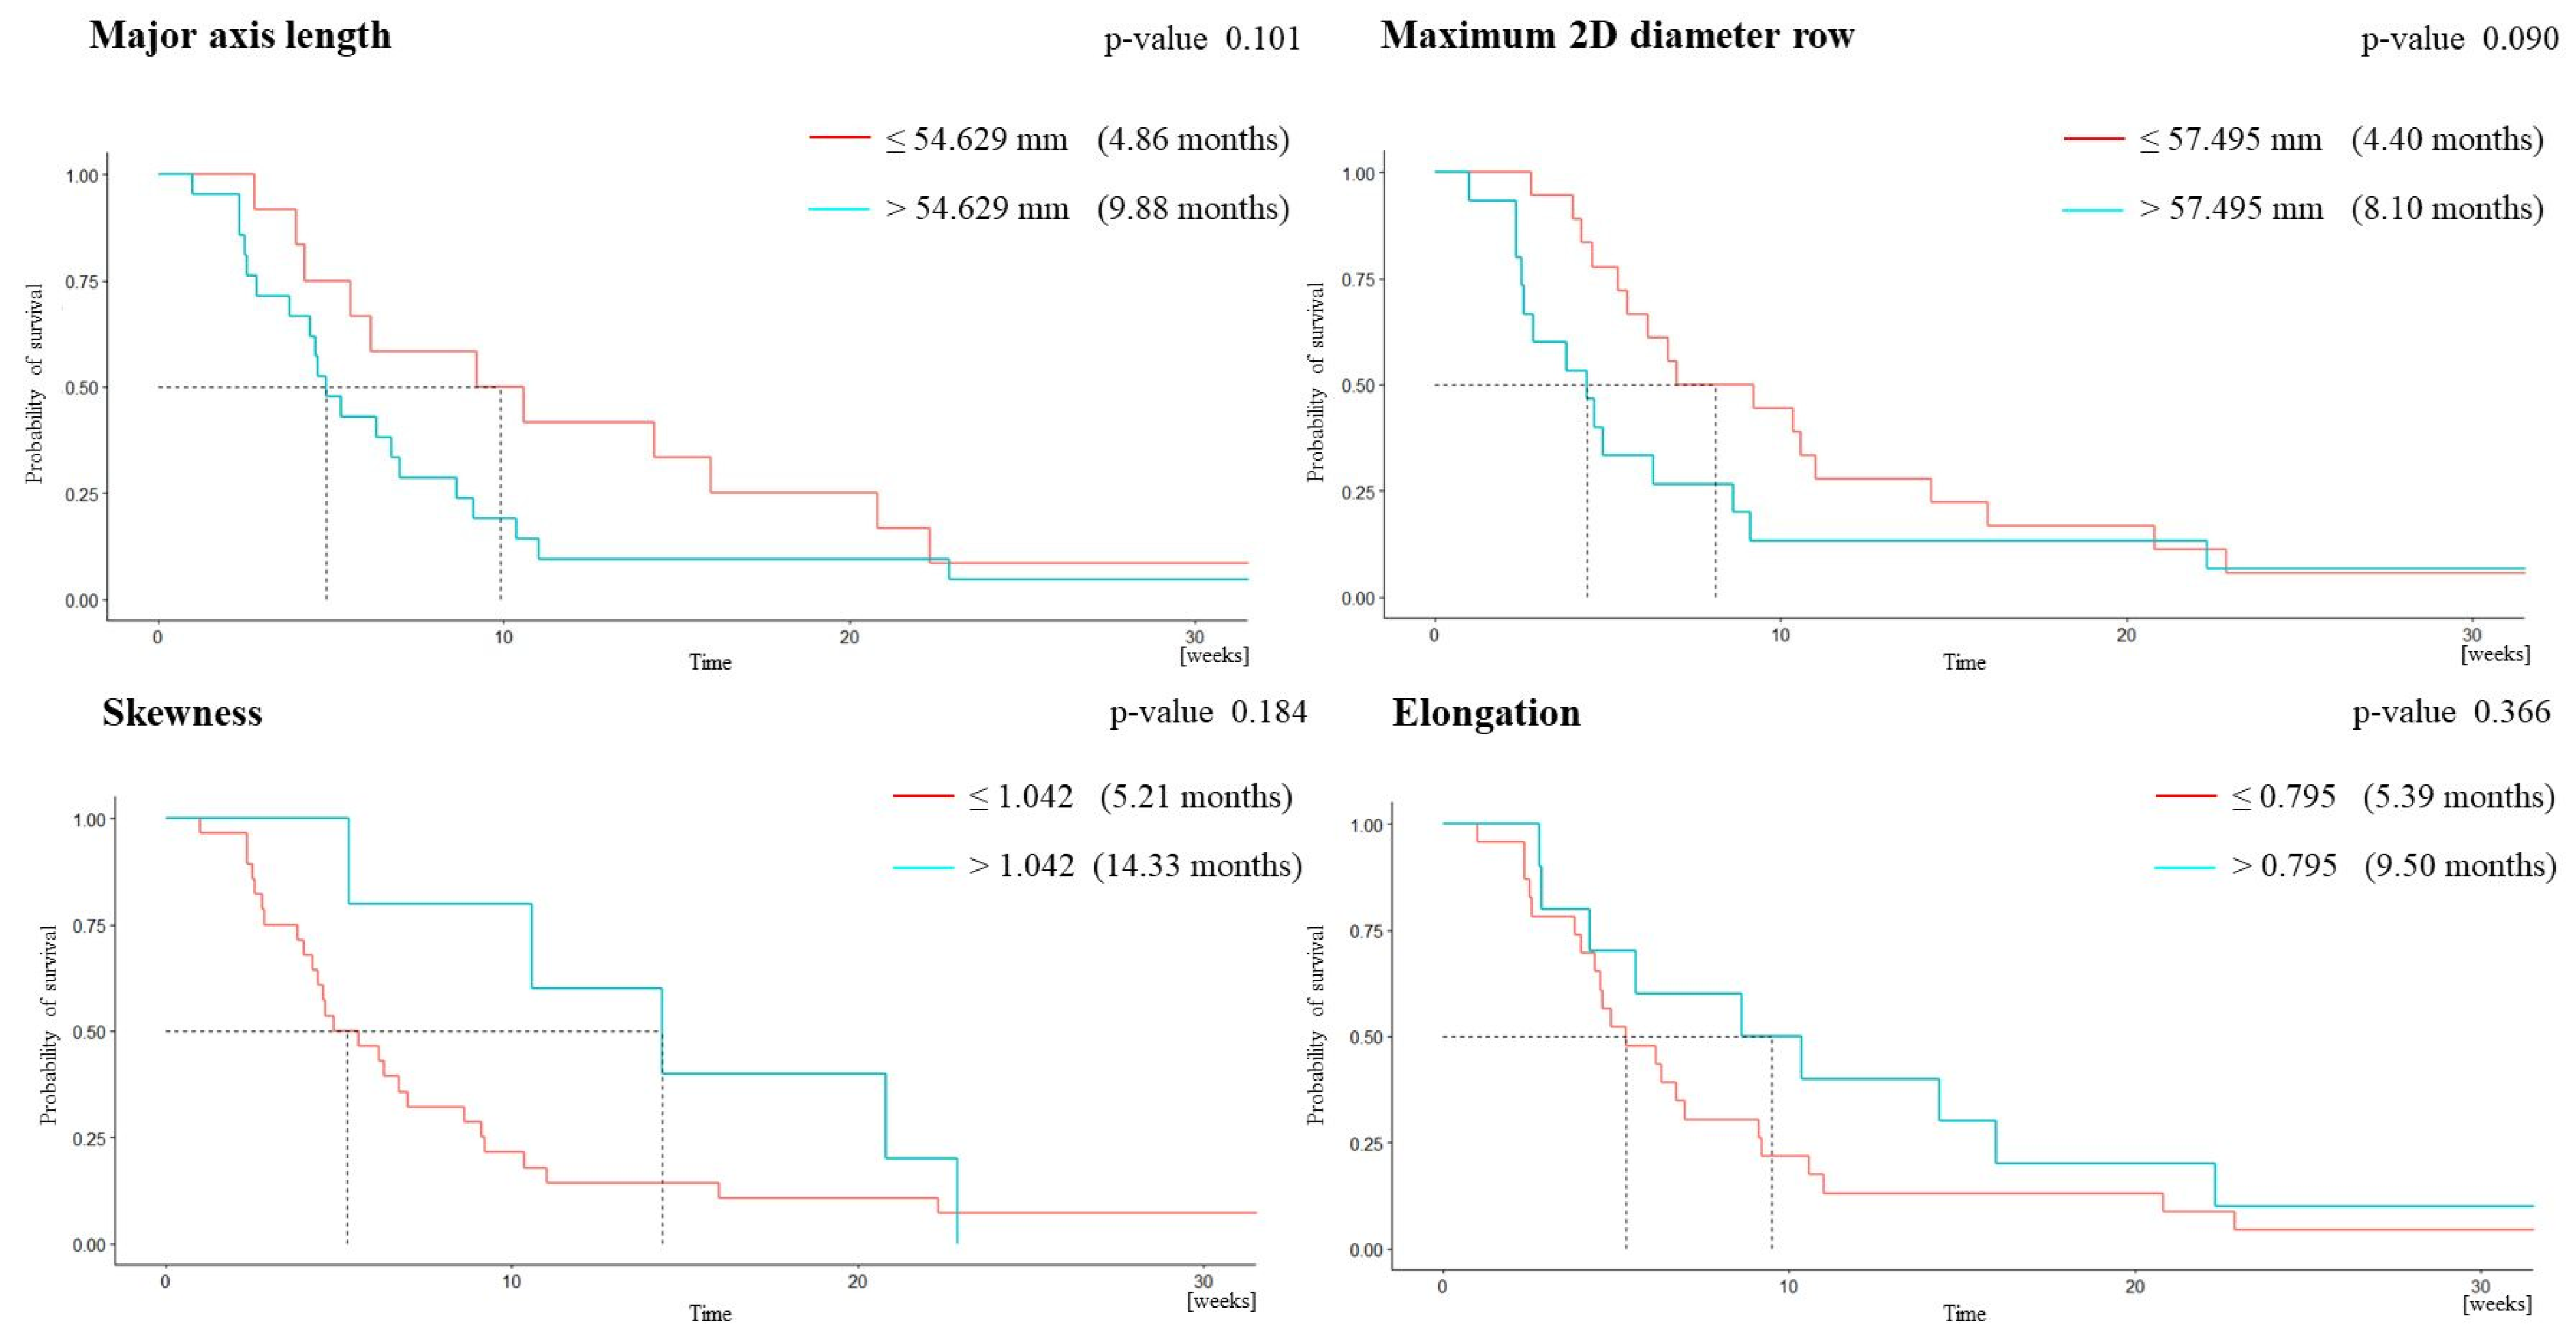

3.2. Survival Analysis

| Feature | Whole Cohort (n = 33) | OS ≤ 1 Year (n = 26) | OS > 1 Year (n = 7) | p-Value |

|---|---|---|---|---|

| MAL | 63.11 ± 21.11 | 66.99 ± 21.55 | 48.68 ± 11.58 | 0.021 |

| Elongation | 0.66 ± 0.17 | 0.63 ± 0.18 | 0.77 ± 0.12 | 0.027 |

| m2Ddr | 56.51 ± 17.82 | 59.12 ± 18.64 | 46.83 ± 10.36 | 0.034 |

| Skewness | 0.68 ± 0.46 | 0.60 ± 0.42 | 0.98 ± 0.48 | 0.043 |

| Univariate Analysis | ||||||

|---|---|---|---|---|---|---|

| AUC | Sensibility | Specificity | PPV | NPV | Cut-Off Value | |

| MAL | 0.788 | 0.714 | 0.731 | 0.417 | 0.905 | 54.629 |

| m2Ddr | 0.712 | 0.714 | 0.5 | 0.278 | 0.867 | 57.495 |

| Skewness | 0.742 | 0.429 | 0.923 | 0.6 | 0.857 | 1.042 |

| Elongation | 0.728 | 0.571 | 0.769 | 0.4 | 0.87 | 0.795 |

| Bivariate Analysis | ||||||

| MAL Skewness | 0.880 | 1.000 | 0.741 | 0.462 | 1 | 96.436 0.653 |

| Trivariate Analysis | ||||||

| m2Ddr Elongation Skewness | 0.895 | 0.833 | 0.852 | 0.556 | 0.958 | |